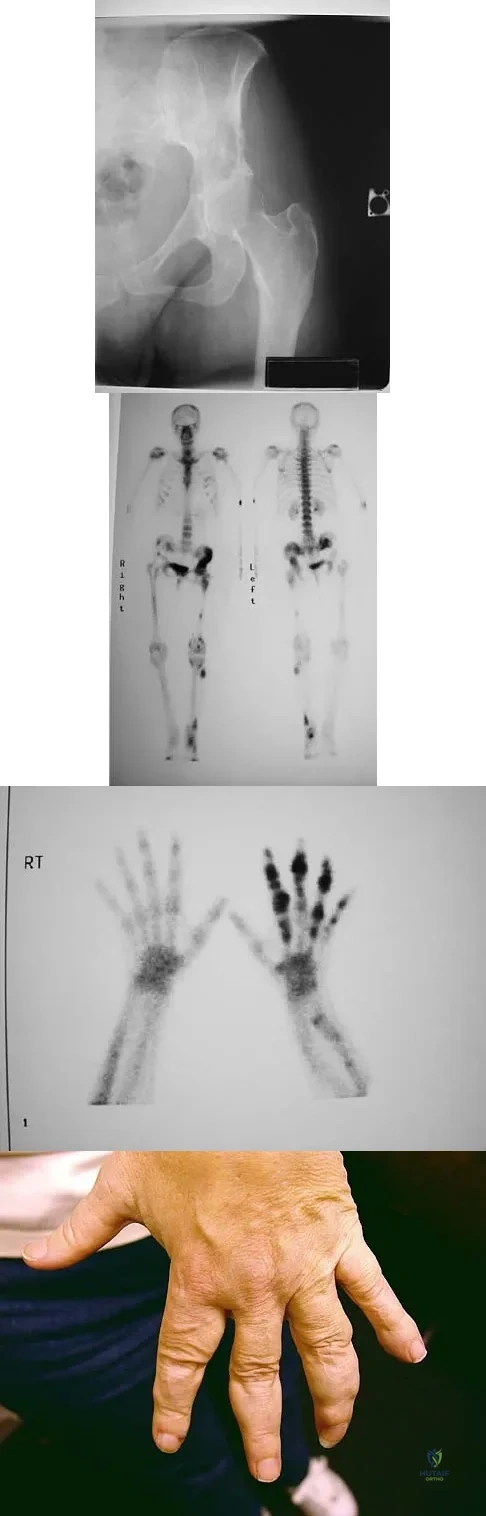

Figure 15a shows the radiograph of a patient who has a chondrosarcoma of the acetabulum. Bone scans are shown in Figures 15b and 15c. Numerous soft subcutaneous masses are present. A clinical photograph of the hand is shown in Figure 15d. What is the most likely diagnosis?

Explanation